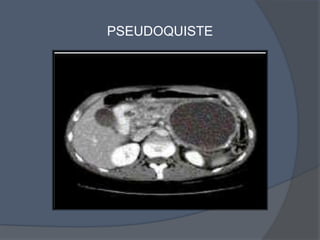

   Pseudoquiste: Formación de densidad líquida caracterizada

por la existencia de un pared de tejido fibroso o granulatoria

y que aparecen 4 semana.

PSEUDOQUISTE